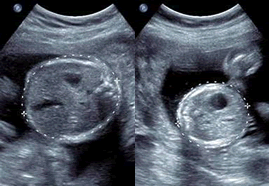

Bất tương xứng cân nặng hai thai trên thai kỳ song thai là một trong những yếu tố chính của kết cục chu sinh, bất kể số bánh nhau. Mặc dù sự khác biệt về cân nặng có thể chỉ là sinh lý bình thường, nhưng nếu chênh lệch cân nặng quá nhiều có thể làm tăng tỷ lệ bệnh và tử vong chu sinh. Đến nay, những nghiên cứu về vấn đề bất tương xứng cân nặng thai và tử vong chu sinh vẫn còn được bàn cãi do kết quả trái chiều.

Một bài tổng quan hệ thống và phân tích gộp về khác biệt cân nặng thai nhi và tử lệ tử vong chu sinh vừa được công bố. Tỷ lệ tử vong chu sinh (PND) bao gồm thai lưu trong tử cung (IUD – được định nghĩa là ít nhất 1 thai chết lưu trong tử cung từ 20 tuần trở lên) và tử vong sơ sinh (NND - trẻ sơ sinh tử vong trong vòng 28 ngày sau sinh). Mức chênh lệch cân nặng hai thai được phân tích ở các mốc >= 15%, >=20%, >= 25% và >=30%. Tổng quan còn đánh giá tỷ lệ tử vong chu sinh theo tuổi thai và cân nặng thai nhi lúc sinh.